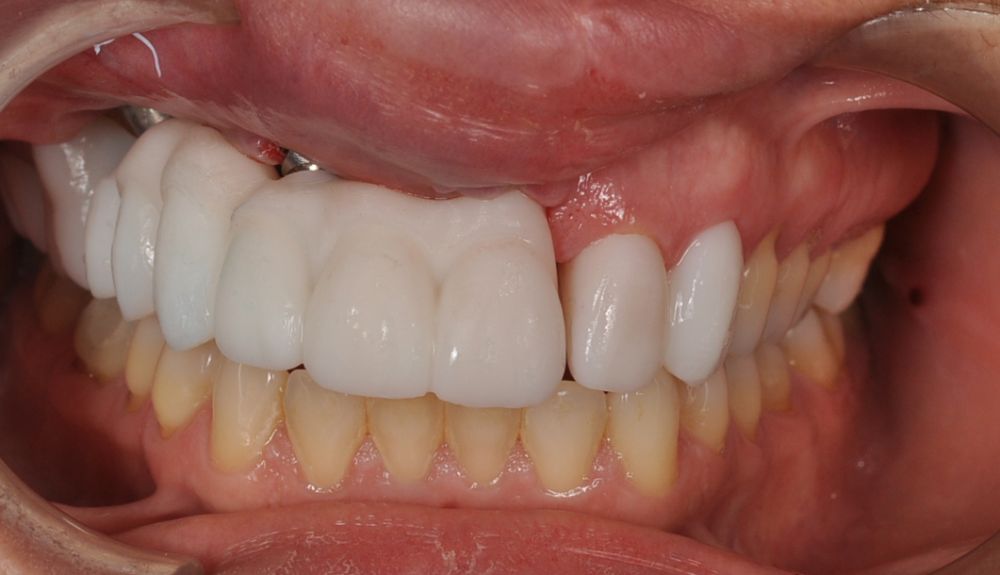

El día de la colocación de las estructuras, se arenó el interior de las coronas dentosoportadas con óxido de aluminio de 50 m y fueron cementadas con cemento de resina Multilink Ò. El puente implantosoportado se atornilló al torque indicado (20Nw) (Figuras 14, 15, 16 y 17).

En el seguimiento a 4 años tras la colocación de la prótesis definitiva, no se observaron complicaciones mecánicas ni biológicas. La paciente continúa libre de enfermedad y con una correcta adaptación al tratamiento rehabilitador implantosoportado (Figura 18).